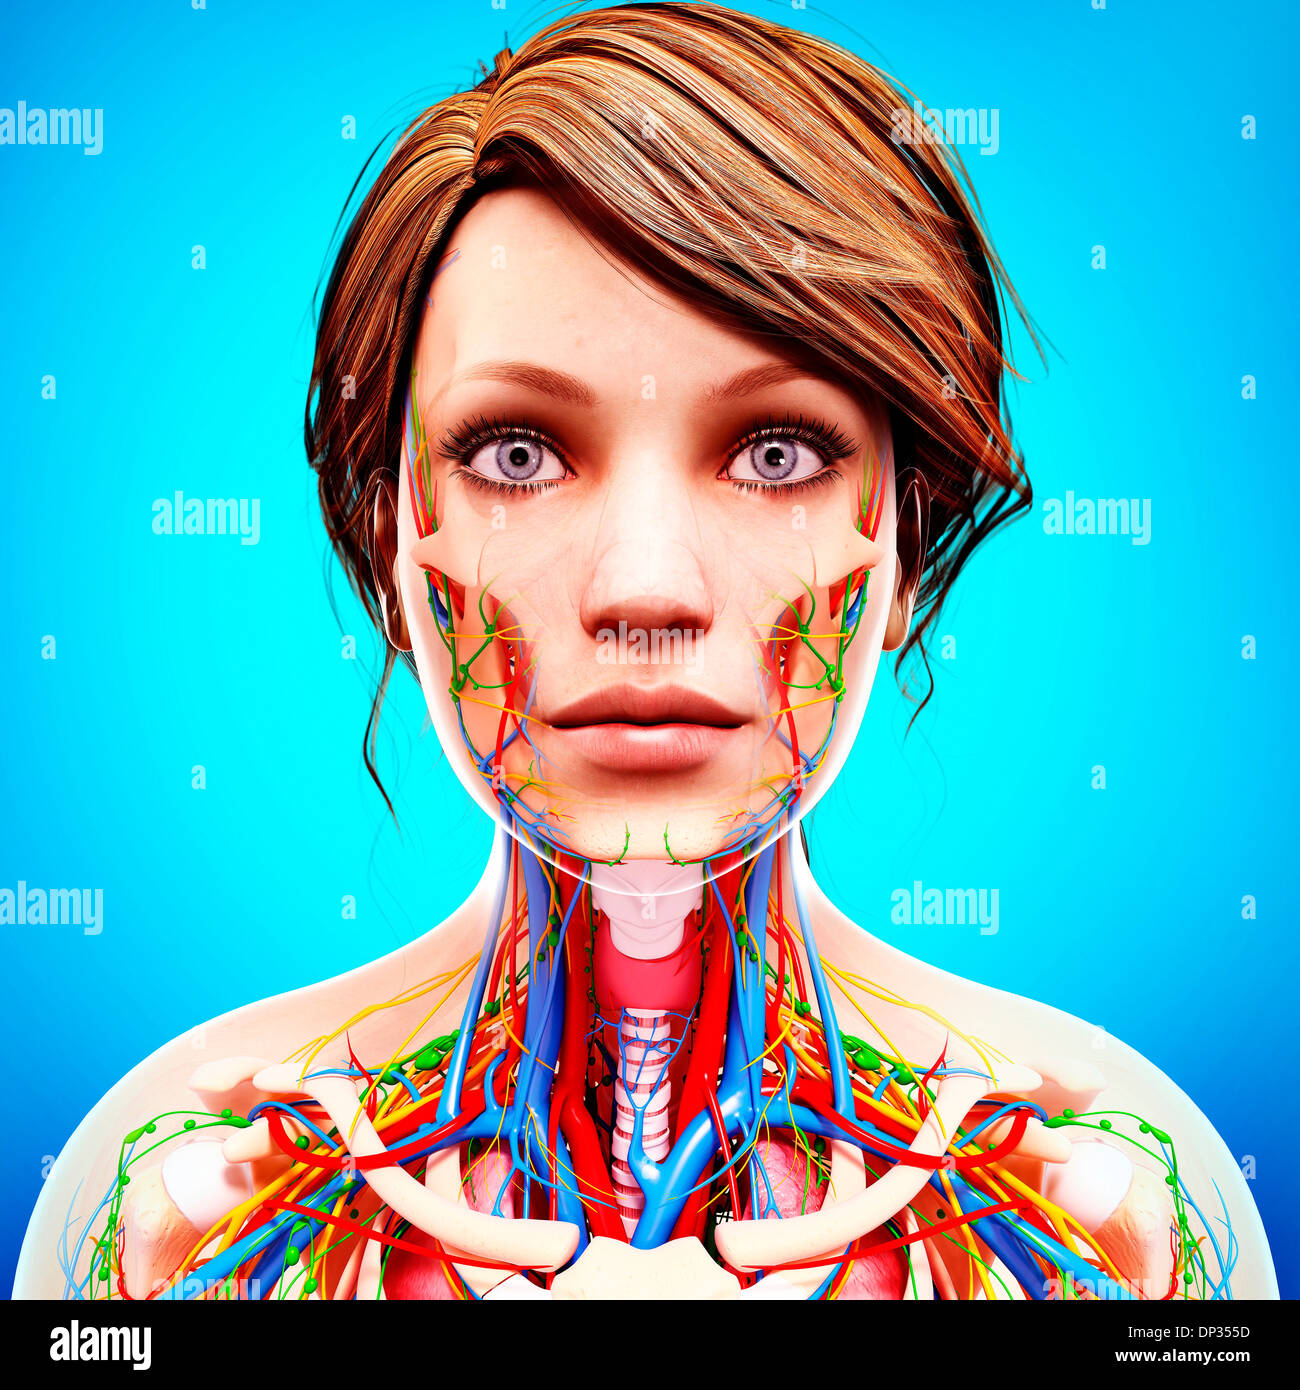

Female Anatomy Photograph By Pixologicstudio/science Photo Library

fineartamerica.comFemale Anatomy Photograph By Pixologicstudio/science Photo Library

fineartamerica.comFemale Anatomy Photograph By Pixologicstudio/science Photo Library

www.alamy.comFemale Anatomy Photograph By Pixologicstudio/science Photo Library

www.alamy.comFemale Anatomy Photograph By Pixologicstudio/science Photo Library

www.alamy.comFemale Anatomy Photograph By Pixologicstudio/science Photo Library

www.alamy.comFemale Anatomy Photograph By Pixologicstudio/science Photo Library

www.alamy.comFemale Anatomy Photograph By Pixologicstudio/science Photo Library

www.alamy.comFemale Anatomy Photograph By Pixologicstudio/science Photo Library

Female Anatomy Photograph By Pixologicstudio/science Photo Library

www.alamy.comFemale Anatomy Photograph By Pixologicstudio/science Photo Library

www.alamy.comFemale Anatomy Photograph By Pixologicstudio/science Photo Library

www.alamy.comFemale Anatomy Photograph By Pixologicstudio/science Photo Library

www.alamy.comFemale Anatomy Photograph By Pixologicstudio/science Photo Library

fineartamerica.comanatomy pixologicstudio artwork 26th

fineartamerica.comanatomy pixologicstudio artwork 26th

www.alamy.comFemale Anatomy Photograph By Pixologicstudio/science Photo Library

www.alamy.comFemale Anatomy Photograph By Pixologicstudio/science Photo Library

www.alamy.comFemale Anatomy Photograph By Pixologicstudio/science Photo Library | Pixels

www.alamy.comFemale Anatomy Photograph By Pixologicstudio/science Photo Library | Pixels